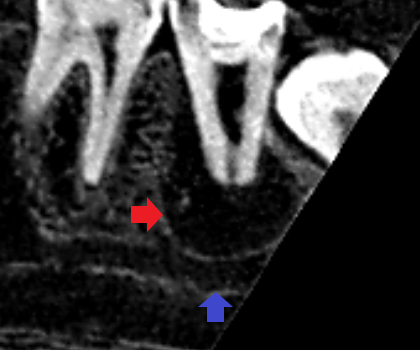

下顎第二大臼歯の初診時の矢状断のCT画像です。

赤い矢印の先に大きな膿の影がみられます。青い矢印の先にみられる下顎管という太い神経の通り道に膿の影が接しており、膿が神経を圧迫して激痛を発していることが考えられました。